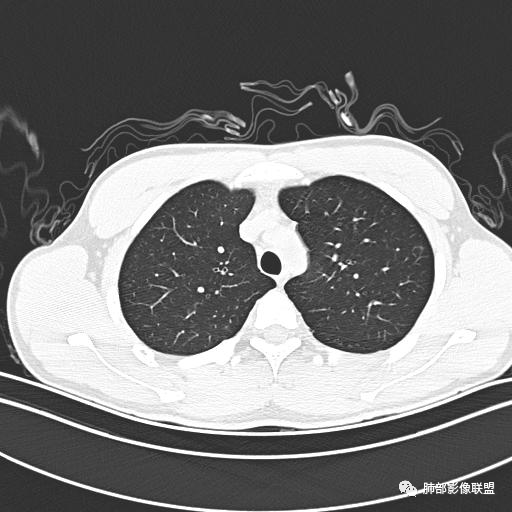

男,19岁

主  诉:发热、全身皮疹2天。

现病史:患者源于2天前受凉后出现发热,最高体温为38.5℃,且颜面部出现少量皮疹,无鼻塞、流涕、咳嗽、咳痰,未在意而未作特殊处理,次日全身皮疹逐渐增多至全身,伴轻度瘙痒,在当地卫生所给予抗病毒、抗感染治疗(具体用药不详)体温有所下降,但皮疹无明显消退,无腹痛、头痛,食欲无明显减退,为进一步诊治,遂于今日急来我院求治,患者目前精神尚可,体力正常,食欲正常,睡眠正常,体重无明显变化,大便正常,排尿正常。

小强:青年,发热,皮疹;双肺散在结节,周围磨玻璃,点晕征,疱疹病毒感染,鉴别荚膜组织胞浆菌,结核。 大雄:青年,急性起病,发热伴全身皮疹2天,抗病毒治疗体温有下降。双肺随机分布大小不等类圆结节,“点晕征”。考虑水痘-疱疹病毒(VZV)血播询问接触史,查体皮疹分布以及形态基本可诊断。 王开金江津中心医院呼吸科:青年男性,起病急,病程短,以发热,皮疹为首发症状,感染指标以单核细胞升高为主,胸部ct双肺多发结界,周围有晕,点晕表现,随机分布,同意於老师意见,水痘疱疹病毒血流感染累及肺。 王秀仙:双肺多发大小不等结节,周围有晕,边缘模糊,呈点晕征表现。青年,急性起病,发热伴全身皮疹2天,抗病毒治疗体温有下降。考虑疱疹病毒。鉴别荚膜组织胞浆菌。 傅昌瑜:19岁男性,发热、全身皮疹2天,单核细胞增高,双肺多发结节,结节边缘见边界不清磨玻璃影。点晕征+发热、全身皮疹+单核细胞增高——考虑水痘-带状疱疹病毒肺炎。 一切∮随缘:年轻男性,发热,皮疹两天,实验室,CRP,PCT增高,影像:双肺多发散在磨玻璃结节,边界欠清,大小不等,呈点晕征改变,以血管束周围分布为主,局部血管束略增粗,其它无明显改变,考虑:1:病毒性肺炎(水痘疱疹病毒?不知道皮肤有无改变)2:真菌(组织胞浆菌,血管侵袭性肺曲霉)3:GPA4:寄生虫(实验室没有看到嗜酸细胞增高) 赵山河:双肺散在结节,周围有晕,边缘模糊,呈点晕征表现。青年,急性起病,发热伴全身皮疹2天,抗病毒治疗体温有下降。考虑水痘—疱疹病毒感染。洪桥爱:青年男性,发热、皮疹2天,伴瘙痒,皮疹于面部首发,之后进展至全身,虽然没有对皮疹进行描述,但是从出疹时间及皮疹进展情况,伴瘙痒,应该就是个水痘患者;CT提示双肺随机分布结节影,部分结节伴有边界不清晕征,考虑水痘血播肺。 刘强:年轻男性,急性起病,皮疹,发热,抗感染治疗体温下降,说明有效。影像表现为散在点晕征,感染类疾病谱(疱疹病毒,真菌,结核),结合年龄,皮肤皮疹,考虑水痘-疱疹病毒性肺炎。 小兜:男性,19岁,发热皮疹两天,颜面部至全身,CRP,降钙素及单核增高。CT示双肺散在小结节,周围伴磨玻璃影,点晕征,考虑为水痘-带状疱疹病毒(varicella-zoster virus,VZV)肺炎 必有路:青年,皮疹+发热+“点晕征”→水痘-疱疹病毒(VZV) 许慧良:青年男性患者,发热、皮疹2天,体温最高38.5℃,第3天皮疹扩展至全身,伴瘙痒,胸部CT:双肺多发随机分布的小结节,结节周边见边界模糊的晕征,考虑水痘病毒感染流心明智:男,19,急性起病,发热伴全身皮疹2天。出疹顺序头→全身,抗病毒有效。胸部CT:两肺多发大小不等类圆形实性小结节影,随机分布,结节周围环绕GGO,边界模糊,呈点晕征。出疹特点是关键,未提示。考虑:血播病毒性肺炎,水痘-疱疹病毒?麻疹?鉴别荚膜组织胞浆菌、TB、血管炎、寄生虫等。 浪迹天涯:病灶多为5-10mm大小结节,结节周围可见磨玻璃样的晕环,常多发,可分布于肺内任何区域,考虑水痘—带状疱疹病肺炎如果短时间内有新的一个区域浸润,更加能说明,